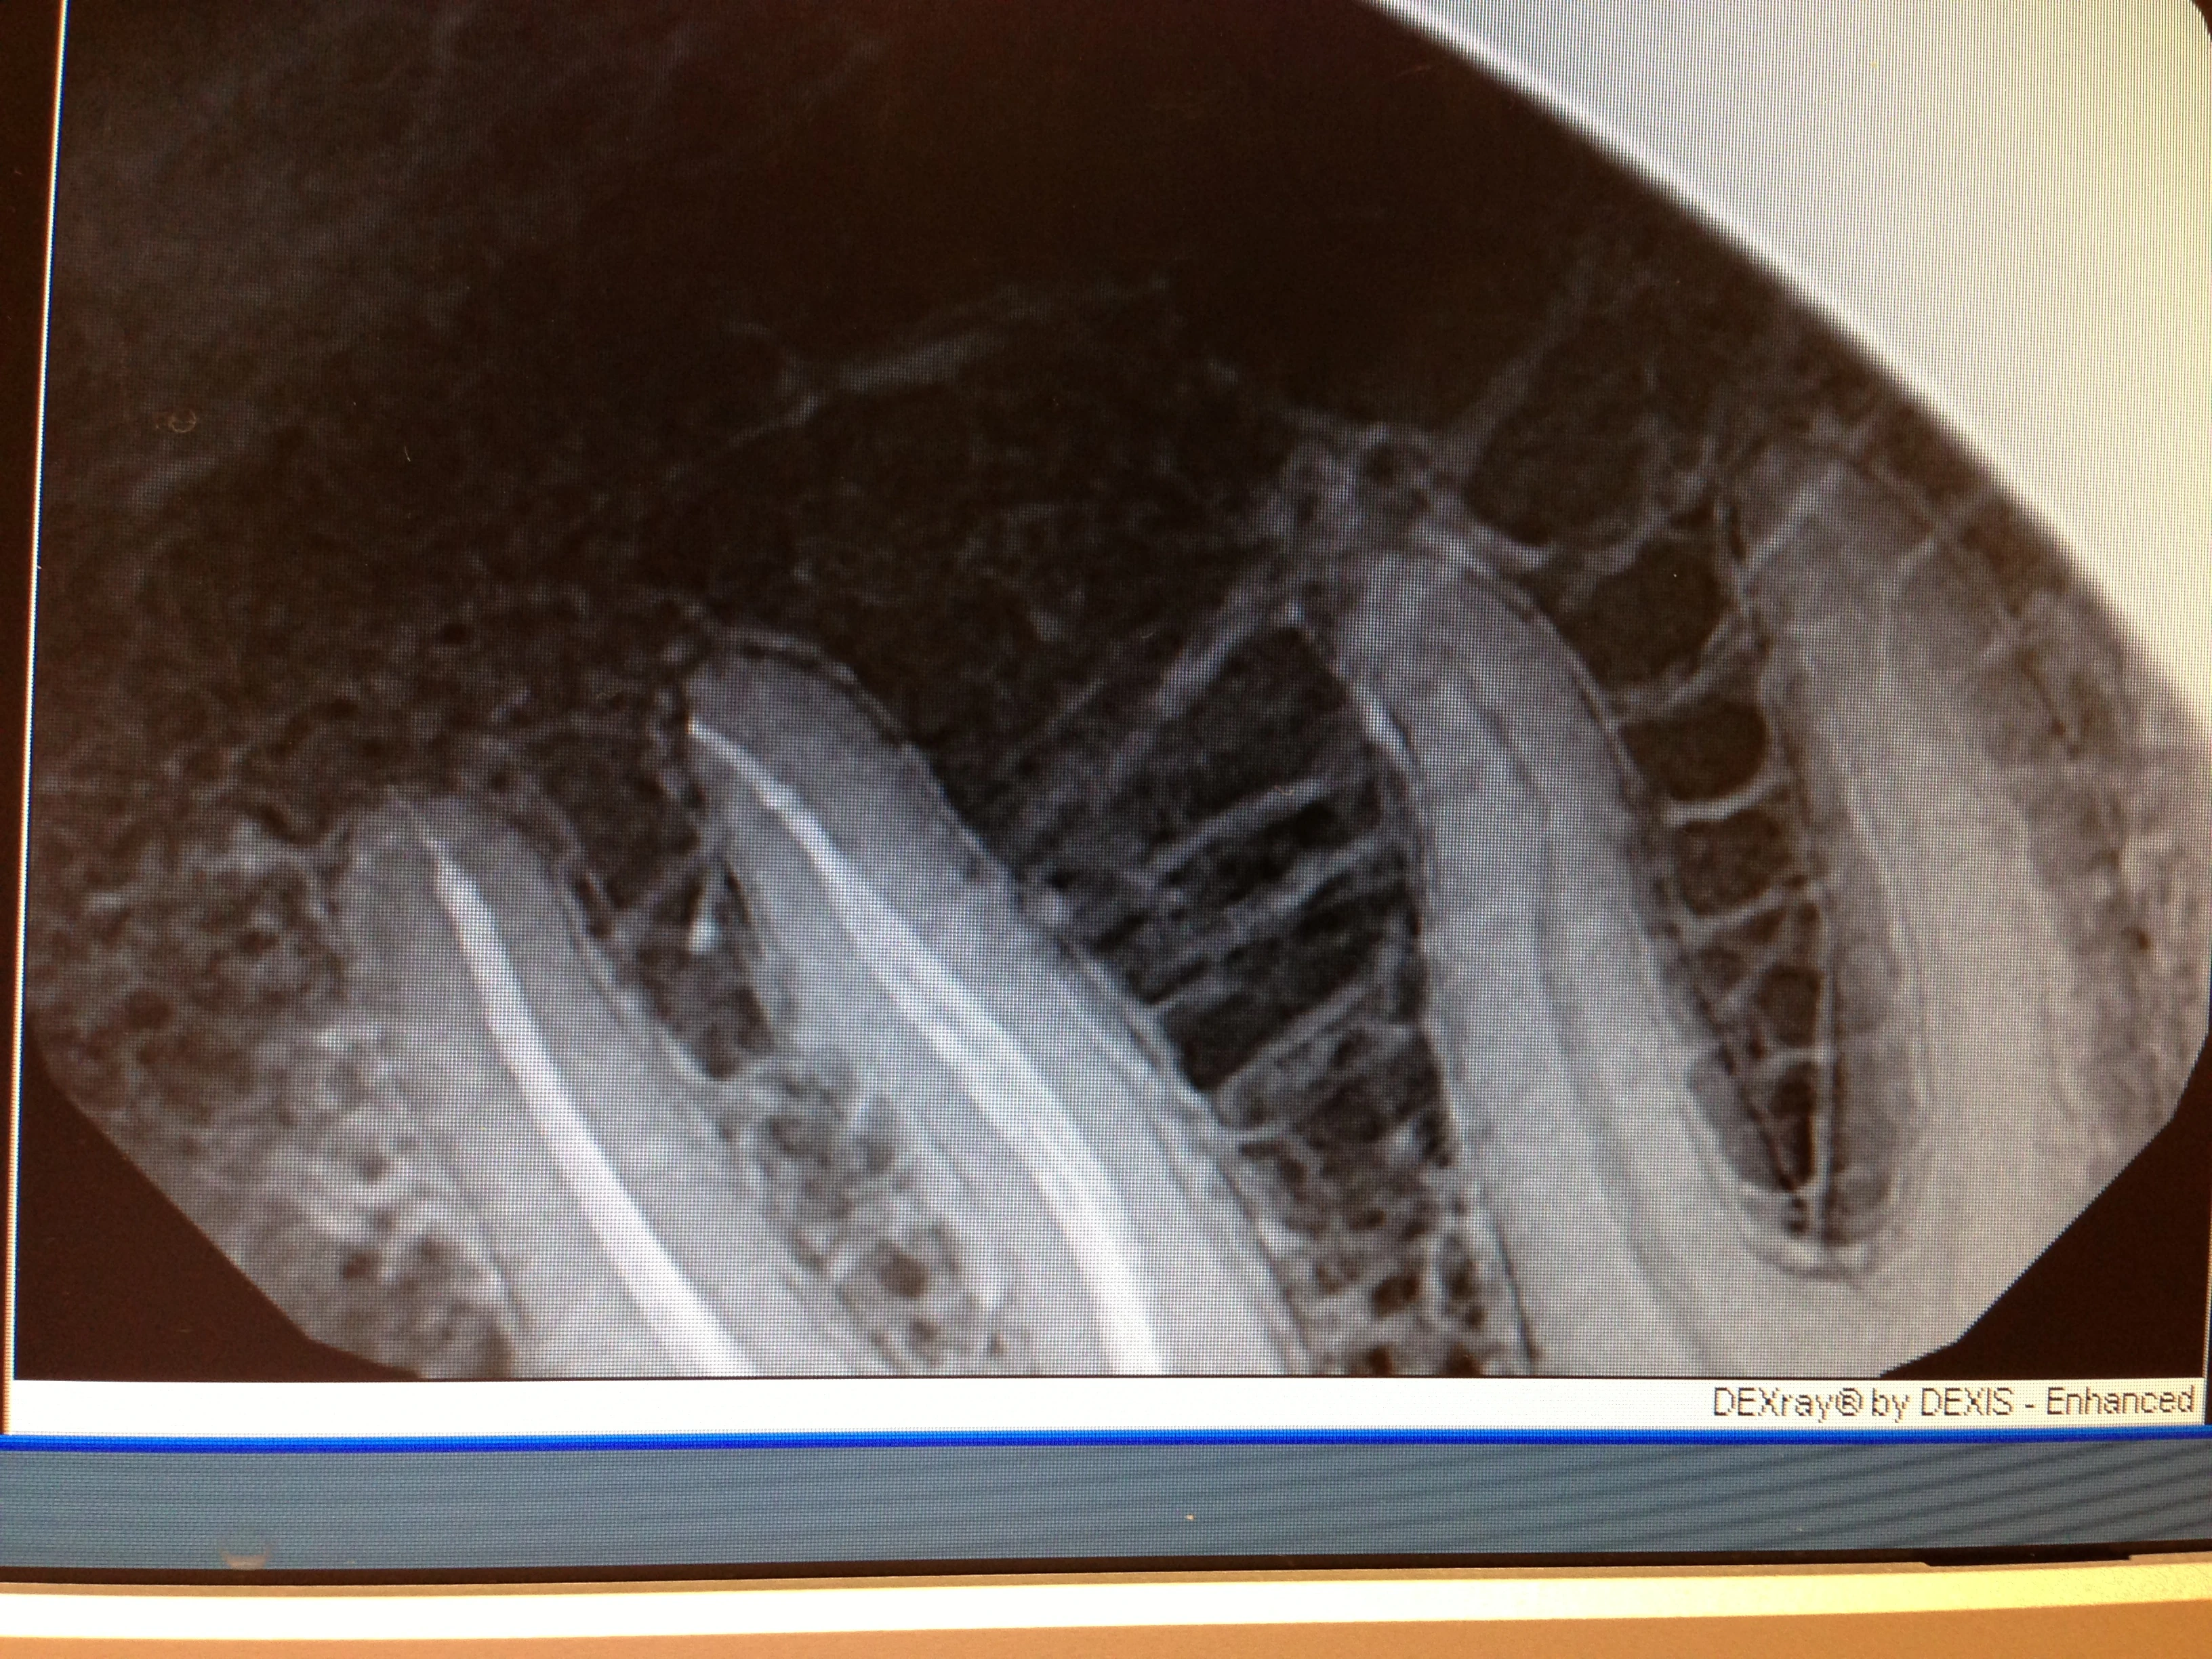

steve, speaking from 20 years of experience in dentistry and 30 years of sucking on the bike, that is one hell of a nice root canal. have enjoyed reading your posts and wish i had a chance to ride with you when i lived back in kansas city.